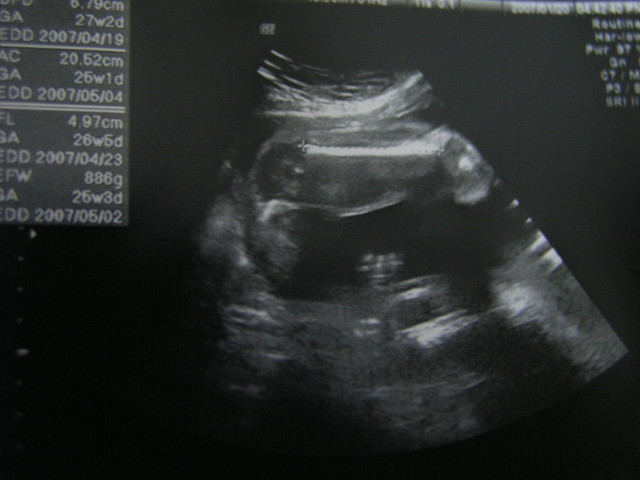

第7次產檢記錄

96/2/23 週數:30週5天

mama體重63KG

心跳Ump-HR:136bpm

頭圍BPD:7.78cm

肚圍AC:26.79CM

大腿骨FL:6.27CM

體重EFW:1784g(2個星期增加 451g)

今天的小蘇菲(Sophie)睡的很香甜

klim說:她覺得小蘇菲越來越可愛了

之前小蘇菲的頭圍都超前2-3週還擔心會是個大頭妹

不過這次居然比上次的小了一丁點

klim說:照超音波只是大約作個預測有一點點的差距是很自然的不要太離譜就好了

而且醫生說很健康沒啥問題!